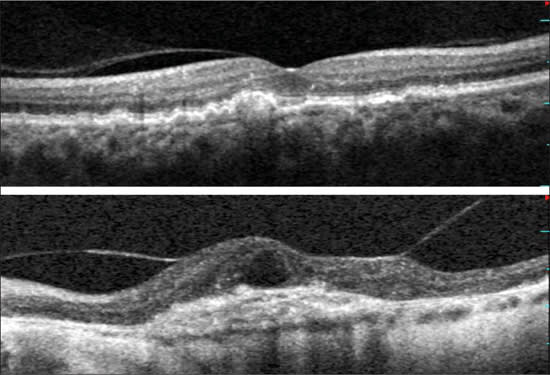

There is a difference between vitreomacular adhesion and vitreomacular traction (Figure 4). Actual vitreomacular traction was also more common in exudative macular degeneration. In eyes with exudative disease, there is a relationship between the location of the CNV complex and the vitreomacular adhesion. This suggests that the exudative process increases adhesion in close proximity.

Figure 4. Classification scheme of hyaloid adhesion and vitreomacular traction seen with spectral optical coherence tomography. Top: Eye with non-exudative age-related macular degeneration and drusenoid detachment: the hyaloid is partially attached over the macula, including the fovea. We considered this as a “no traction” configuration, since no distortion is visible on the retinal surface and the angle of insertion of the hyaloid onto the retina is not steep. Bottom: Eye with choroidal neovascularization. The persistence of hyaloid adhesion causes vitreomacular traction over the choroidal neovascularization complex: a focal distortion of the retinal profile is visible at the site of hyaloid attachment.